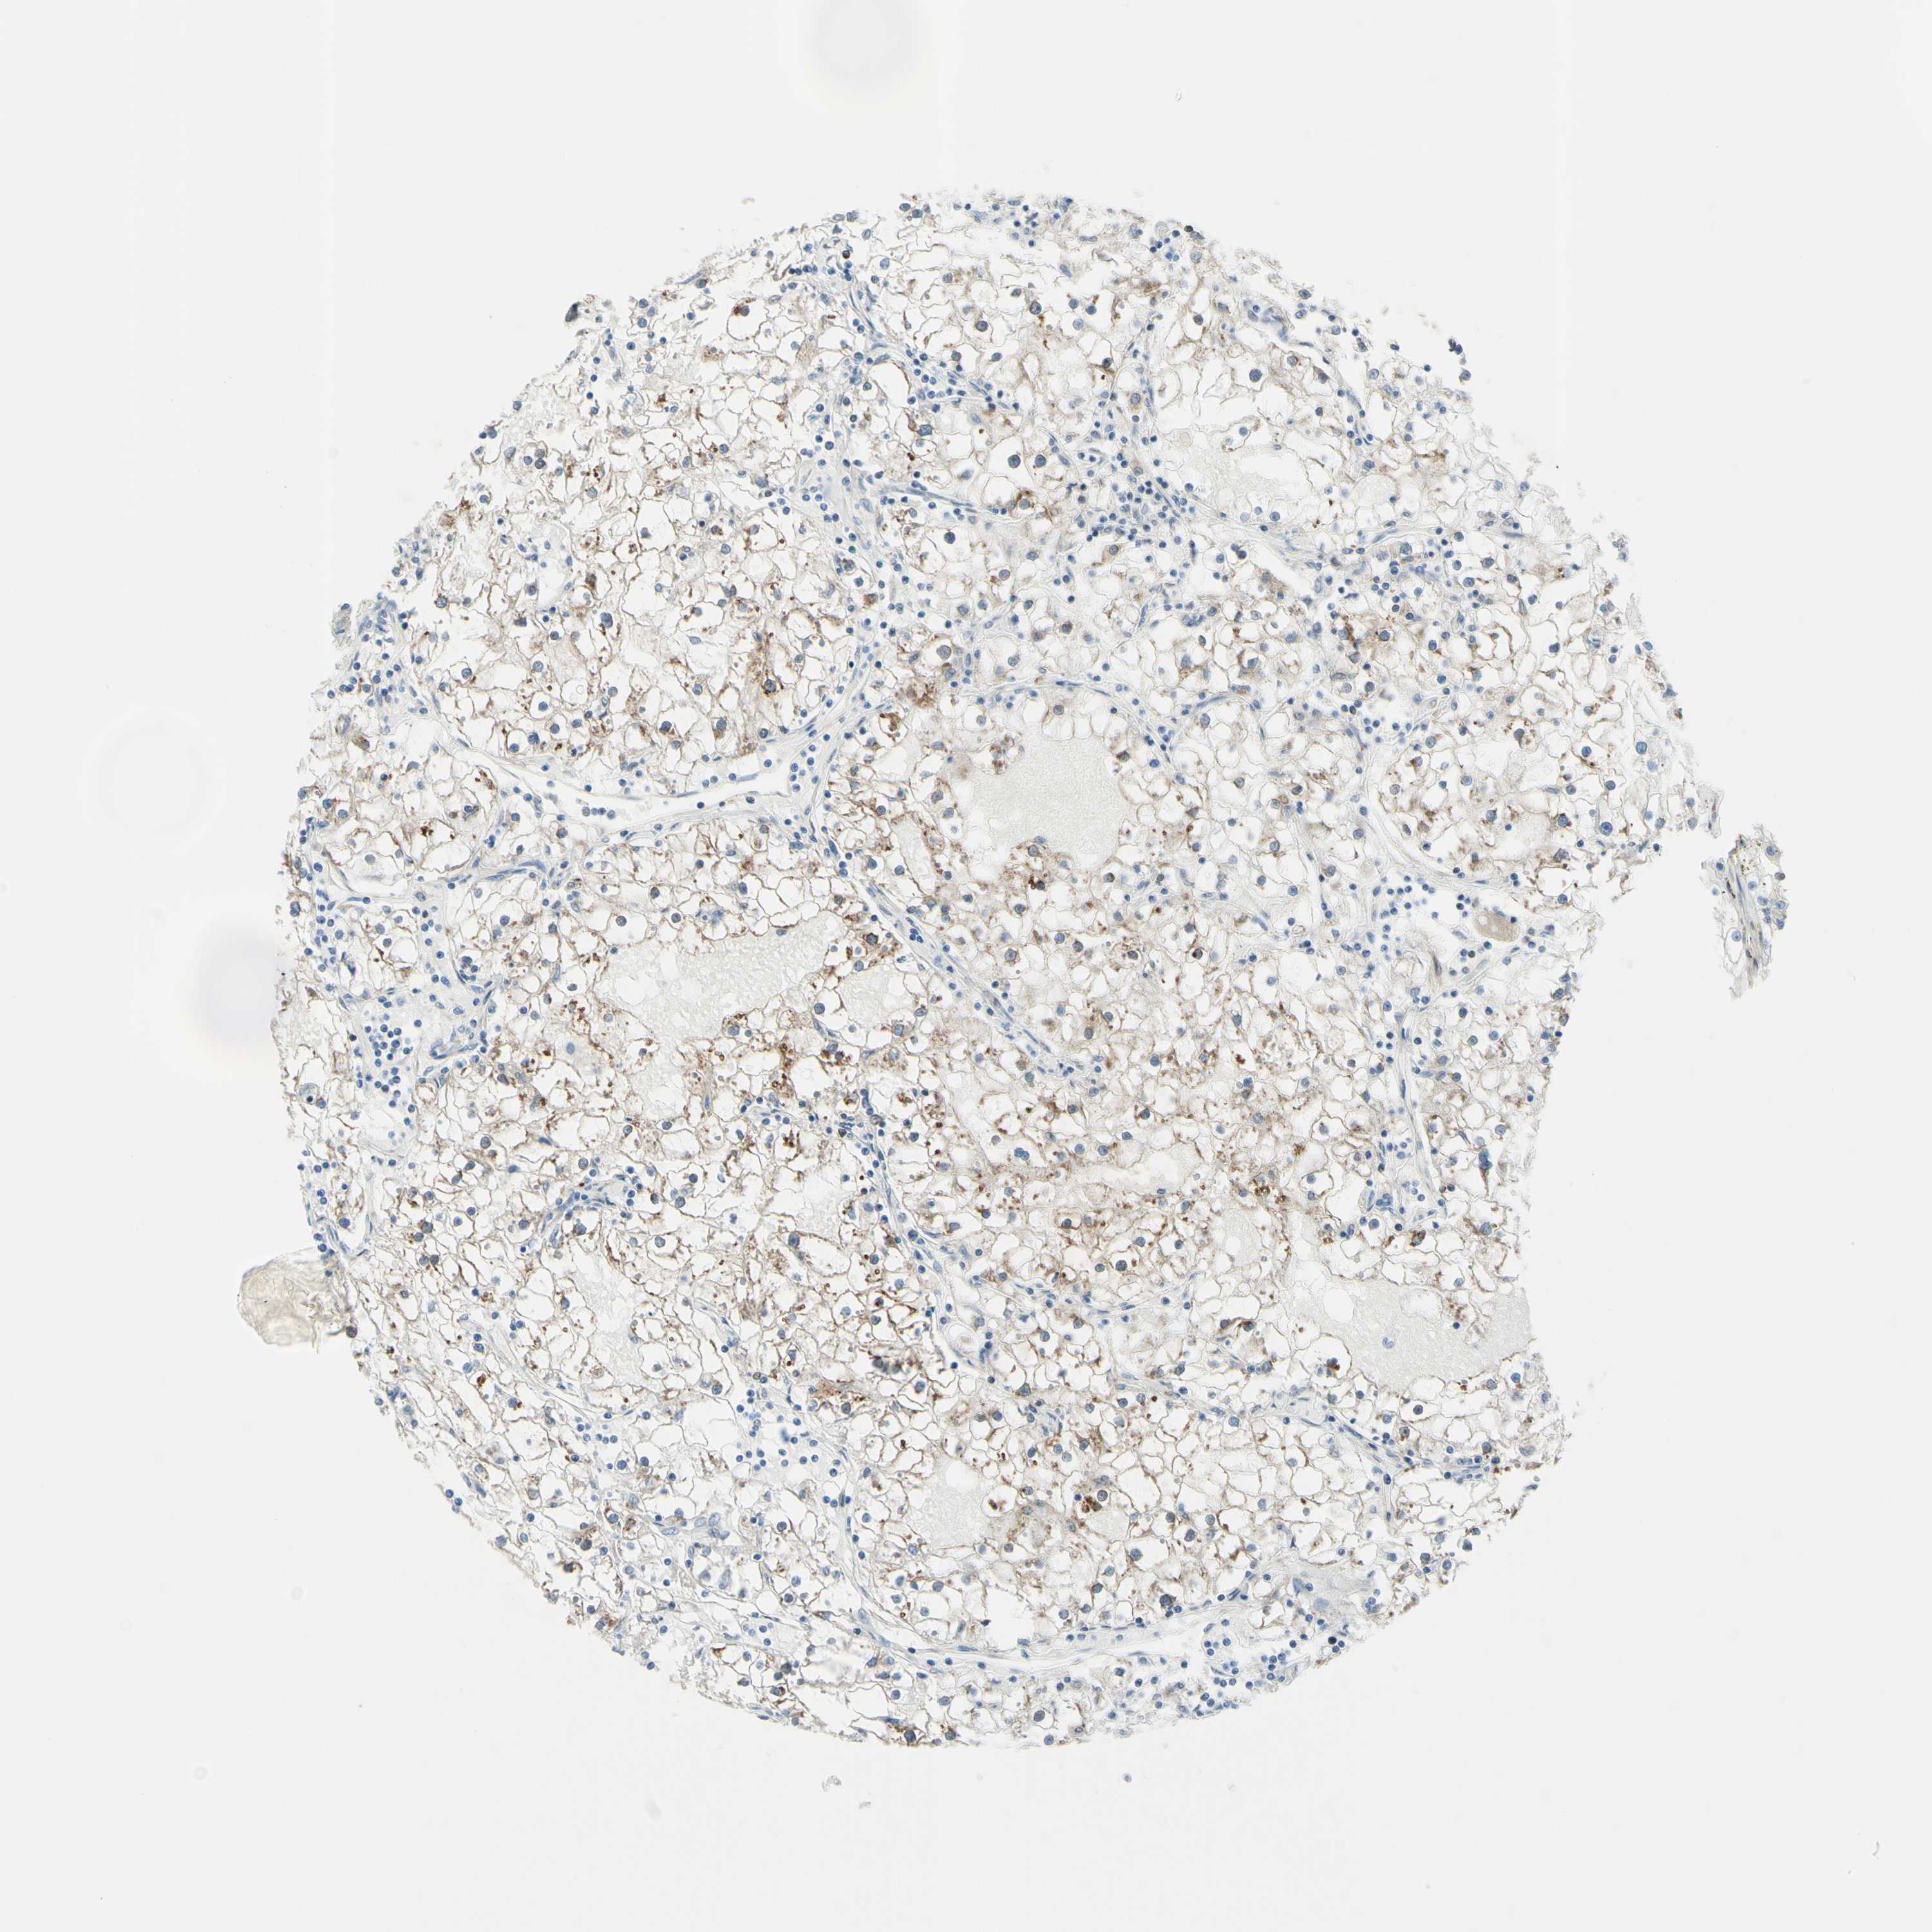

KIDNEY RENAL CLEAR CELL CARCINOMA (TCGA) - Interactive survival scatter ploti

The Survival Scatter plot shows the clinical status (i.e. dead or alive) for all individuals in the patient cohort, based on the same data that underlies the corresponding Kaplan-Meier plots. Patients that are alive at last time for follow-up are shown in blue and patients who have died during the study are shown in red.

The x-axis shows the expression levels (FPKM) of the investigated gene in the tumor tissue at the time of diagnosis. The y-axis shows the follow-up time after diagnosis (years). Both axes are complimented with kernel density curves demonstrating the data density over the axes. The top density plot shows the expression levels (FPKM) distribution among dead (red) and alive patients (blue). The right density plot shows the data density of the survived years of dead patients with high and low expression levels respectively, stratified using the cutoff indicated by the vertical dashed line through the Survival Scatter plot. This cutoff is automatically defined based on the FPKM cutoff that minimizes the p-score. The cutoff can be changed by dragging the vertical line or by entering a cutoff value in the square labeled "Current cut-off".

Under the Survival Scatter plot the p-score landscape (black curve; left axis) is shown together with dead median separation (red curve; right axis). Dead median separation is the difference in median mRNA expression between patients who have died with high and low expression, respectively. It is calculated as follows: median FPKM expression of dead patients with high expression - median FPKM expression of dead patients with low expression. This is intended to aid the user in visually exploring custom cutoffs and the associated p-scores and dead median separation.

Individual patient data is displayed and can be filtered by clicking on one or more of the category buttons on the top of the page. Categories describing expression level and patient information include: high, low, alive, dead, female, male and tumor stages. The scale of the x-axis can be toggled between linear and log-scale by clicking on the "x log" button. Mouse-over function shows TCGA ID, patient information and mRNA expression (FPKM) for each patient.

& Survival analysisi

Kaplan-Meier plots summarize results from analysis of correlation between mRNA expression level and patient survival. Patients were divided based on level of expression into one of the two groups "low" (under cut off) or "high" (over cut off). X-axis shows time for survival (years) and y-axis shows the probability of survival, where 1.0 corresponds to 100 percent.

TRAF2 is not prognostic in Kidney Renal Clear Cell Carcinoma (TCGA)

: 18

Average pTPM 15.3

Number of samples 521